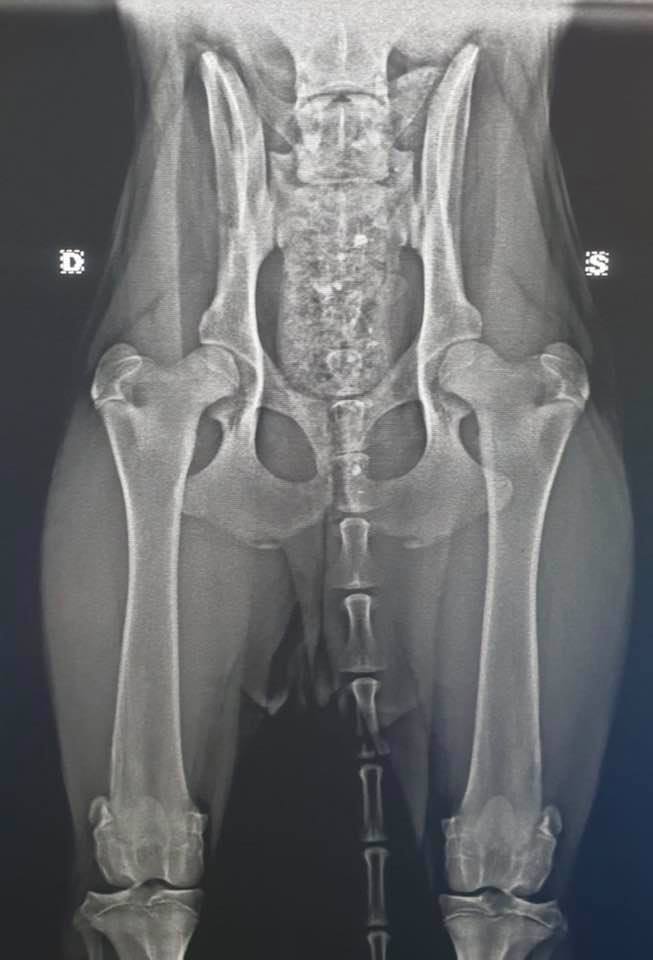

Röntgen in einer Klinik die sich mit Zuchtuntersuchungen auch auskennt.

HD, ED, OCD sowie deren Befundauswertungen über einen anerkannten geprüften Gutachter.

Hinzu kommt seit kurzer Zeit noch LÜW - der Lendenübergangswirbel, der ebenfalls zum Röntgenprotokoll zählt und entsprechend dann über einen Gutachter ausgewertet werden sollte.